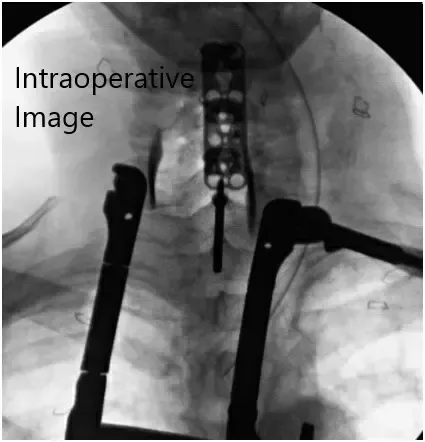

Imágenes fluoroscópicas intraoperatorias.

Aplicamos lordosis usando el doblador lordótico portátil a la placa y usando fluoroscopia para asegurar el tamaño adecuado de la placa. La placa cervical se colocó hacia adelante y luego se usaron tornillos de 4,2 x 16 mm en los cuerpos vertebrales C3, C4, C5 y C6. Realizamos fluoroscopia durante todo el proceso para asegurar la trayectoria correcta de los tornillos.